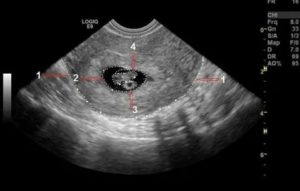

На УЗ-снимке: в полости матки определяются 2 плодных яйца с живыми эмбрионами

При диаметре плодного яйца 20 мм и больше должны визуализироваться эмбрион и желточный мешок. В обратном случае говорят об анэмбрионии. Жизнеспособность зародыша оценивают по его сердцебиению.

При копчико-теменном размере эмбриона 6 мм и более в обязательном порядке должно регистрироваться его сердцебиение. Если оно отсутствует, то это свидетельствует о гибели плода.

В плодном яйце уже должны визуализироваться эмбрион и желточный мешок. Располагаясь эксцентрично, они формируют изображение на мониторе в виде двойного пузырька. Желточный мешок определяется как округлое тонкостенное образование с анэхогенным содержимым внутри.

Внутренний диаметр плодного яйца в этом сроке составляет порядка 22 миллиметров. Начиная с 5 недель беременности его размер увеличивается на 1-2 мм.